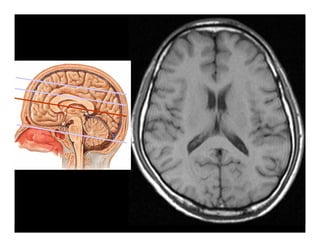

Giải phẫu

Tổn thương